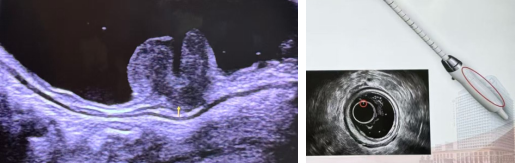

经直肠超声检查是将超声探头放入肛门内,利用超声波在肛门及直肠内部进行扫描形成图像,帮助医生发现那些隐藏在肛肠内的病变的检查。

直肠超声的优势在于它的准确性和无创性。它能够帮助医生准确确定病灶位置、大小和深度,尤其是360°环扫经直肠腔内超声,可全方位对肛管和直肠壁进行探查,环状扫描视野更清晰,这些信息对于制定治疗方案至关重要。而且,直肠超声检查无需担心辐射问题,价格低廉,方便快捷。